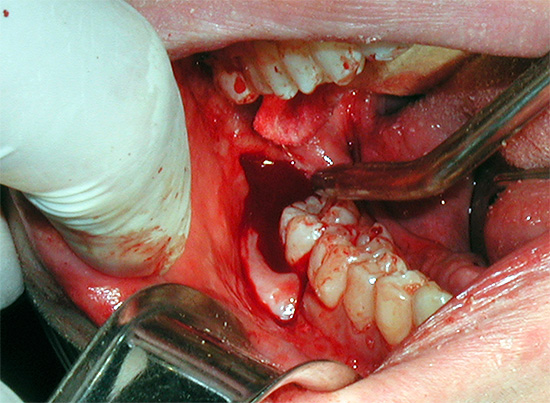

Foto dei denti del giudizio rimossi:

La foto mostra un esempio di flemmone (infiammazione purulenta versata acuta):

Nella foto - un dente del giudizio rimosso in alcune parti: